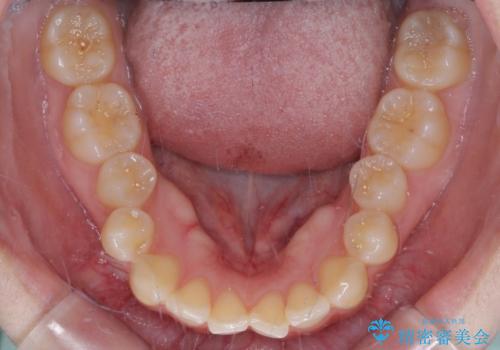

- 左上の前歯が出ていることを主訴として来院された患者様です。

当初はインビザラインを希望されていましたが、職業柄お茶する機会が多く装着時間を確保することが難しいとのことで、相談の上ワイヤー矯正の中では目立ちにくい審美装置で矯正を進めていくこととしました。